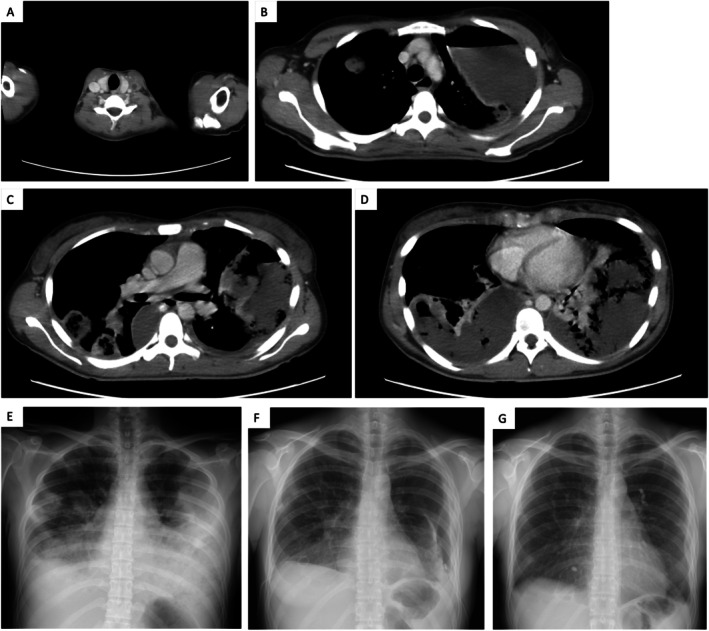

Lemierre's syndrome is a rare condition characterised by internal jugular vein thrombophlebitis and bacteremia caused by anaerobic organisms following an oropharyngeal infection. We report the case of a 29-year-old woman who presented with fever, sore throat, dyspnea, and chest pain. Chest computed tomography (CT) revealed lung suppuration, pneumothorax, and thrombosis of the left internal jugular vein, confirming the diagnosis of Lemierre's syndrome. During treatment, she developed pyothorax with bronchopleural fistulas and intractable pneumothorax. Although antibiotics and thoracic drainage controlled the infection, persistent air leakage and incomplete lung expansion remained. Placement of an endobronchial watanabe spigot (EWS) successfully resolved the air leak, allowing the patient to avoid surgery and be discharged. This case highlights the effectiveness of EWS in managing intractable pyopneumothorax secondary to Lemierre's syndrome.